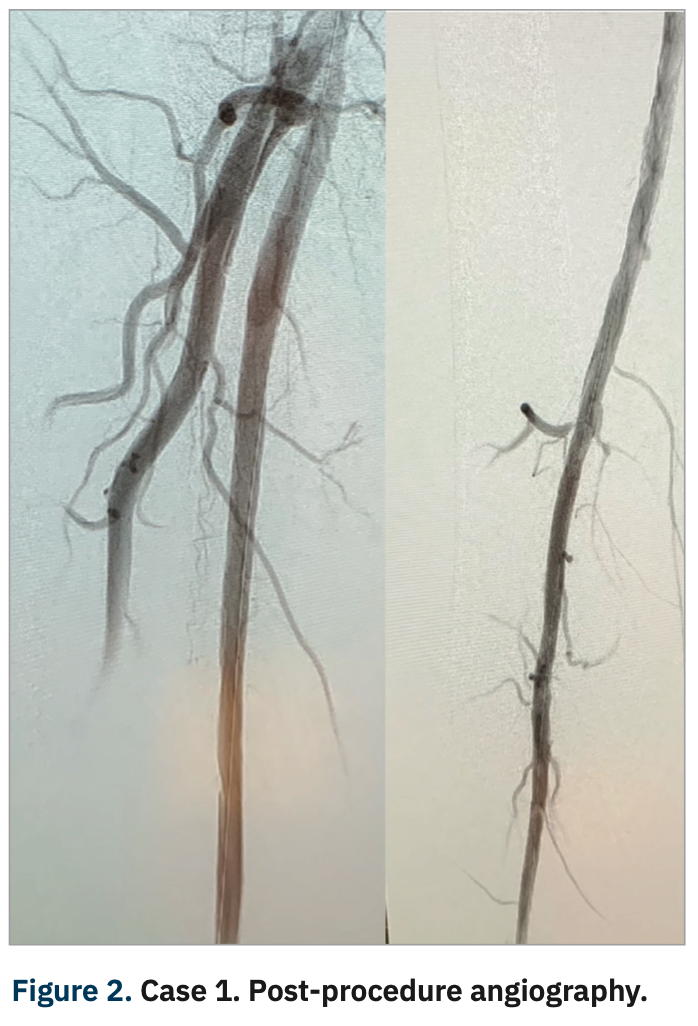

Post angioplasty, a completion angiogram was performed (Figure 5), showing complete resolution of the disease, with in-line flow now extending through the CFA and SFA into the popliteal artery and down into the foot via the posterior tibial artery. The patient was subsequently discharged home on dual antiplatelet therapy. After repeat debridement, the patient’s ulcers healed and he is no longer having associated pain. He has maintained a palpable posterior tibial on repeat exam and will continue to be monitored with serial duplex studies to follow his arterial pathology.